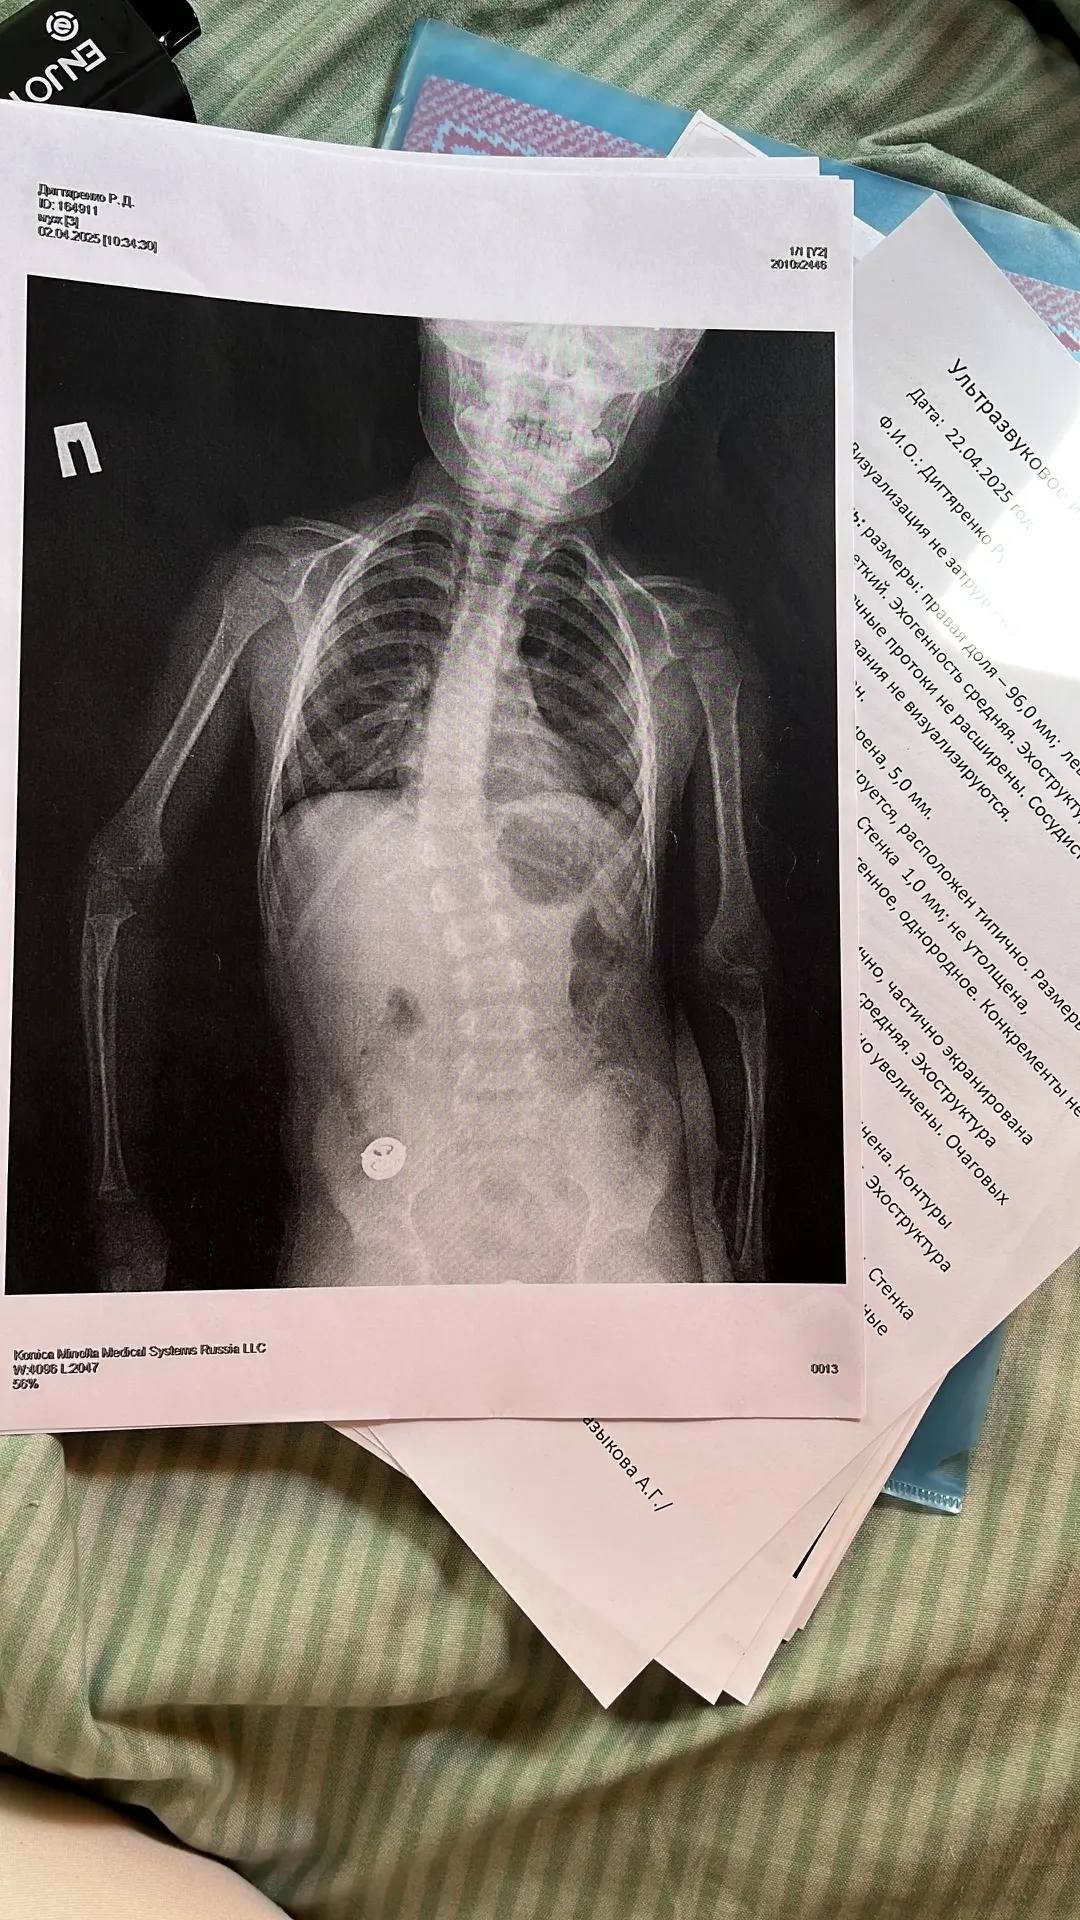

Нужно собрать помощь для ребёнка на операцию на позвоночнике. Ему 3.5 года.